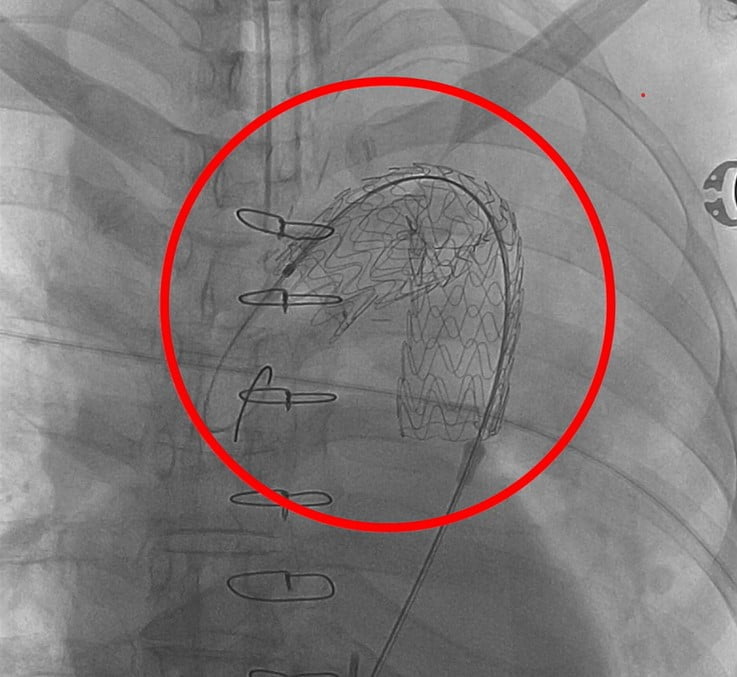

Frozen Elephant Trunk